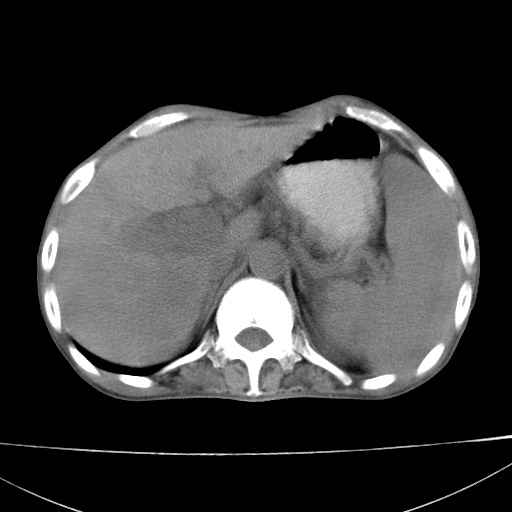

患者 男  41岁,右上腹痛伴腹泻10天,8年前有乙肝,本次b超查肝右叶占位来做ct ,请会诊!

肝硬化\\脾大\\门静脉高压,胃底静脉曲张可能性大.肝右叶肝癌肝内转移,建议增强.左侧小结石.

肝右叶肝癌肝内转移,建议增强

支持肝癌伴肝内转移,脾大,门静脉高压,胃底静脉曲张。

1)考虑肝癌;建议行ct增强扫描检查。2)脾大,门静脉高压,胃底静脉曲张。3)左肾小结石。

1)考虑肝癌及门脉瘤栓,建议行ct增强扫描检查。2)脾大,门静脉高压,胃底静脉曲张。3)左肾小结石。

结合病史;考虑肝癌。门静脉高压,脾大。胃底静脉曲张。

1)考虑肝癌;2)脾大,门静脉高压,胃底静脉曲张。3)左肾小结石。建议行ct增强扫描检查。